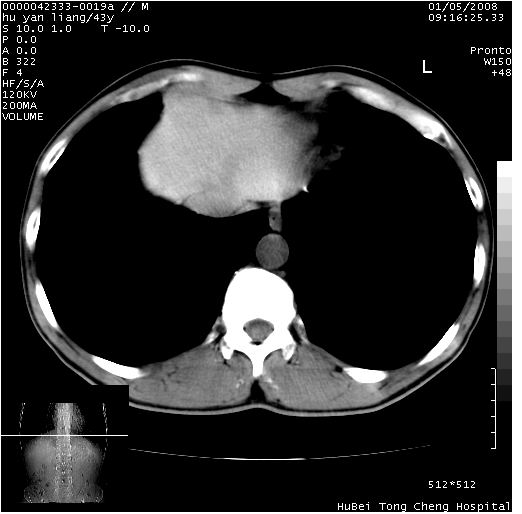

患者 男,43岁。右上腹不适1年余。既往有“肝右叶肝脓肿”病史,经保守治疗后痊愈。

b超提示:1)肝右叶肝内胆管结石。2)肝右叶占位性病变待排。

上中腹部ct轴位平扫+增强扫描(层厚10mm,螺距1.0,重建间隔10mm),图像如下:

肝右上叶偏后方较大团片状钙化灶,支持:肝脓肿后遗改变!